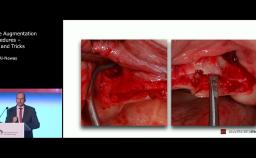

The congress lecture will discuss two techniques for sinus floor elevation (SFE) in implant dentistry: the lateral window technique and the transalveolar technique. Choice of method depends on anatomical considerations such as residual bone. Both methods show high implant survival rates, comparable to native bone (around 95%). Transalveolar SFE is suited for cases with enough residual bone and a flat sinus floor, but risks Schneiderian membrane perforation due to incomplete osteotomy. Advances in surgical instruments, including drills with safety ends and controlled hydraulic pressure, have reduced perforation risks in transalveolar SFE. However, for severely resorbed ridges or the presence of septa, the lateral window technique is preferred. The lecture will cover how to select the appropriate technique for each patient.